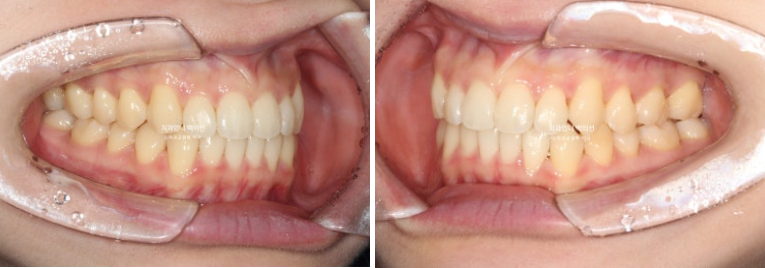

23.07~25.04

배열은 좋고

결손치 쪽으로 돌아가있던 상악 중심선은 아래중심선과도 만나게 되었습니다.

스마일라인이 특히나 귀여운 분

코과 인중에 맞춰진 앞니 중심선을 보니 편안합니다.